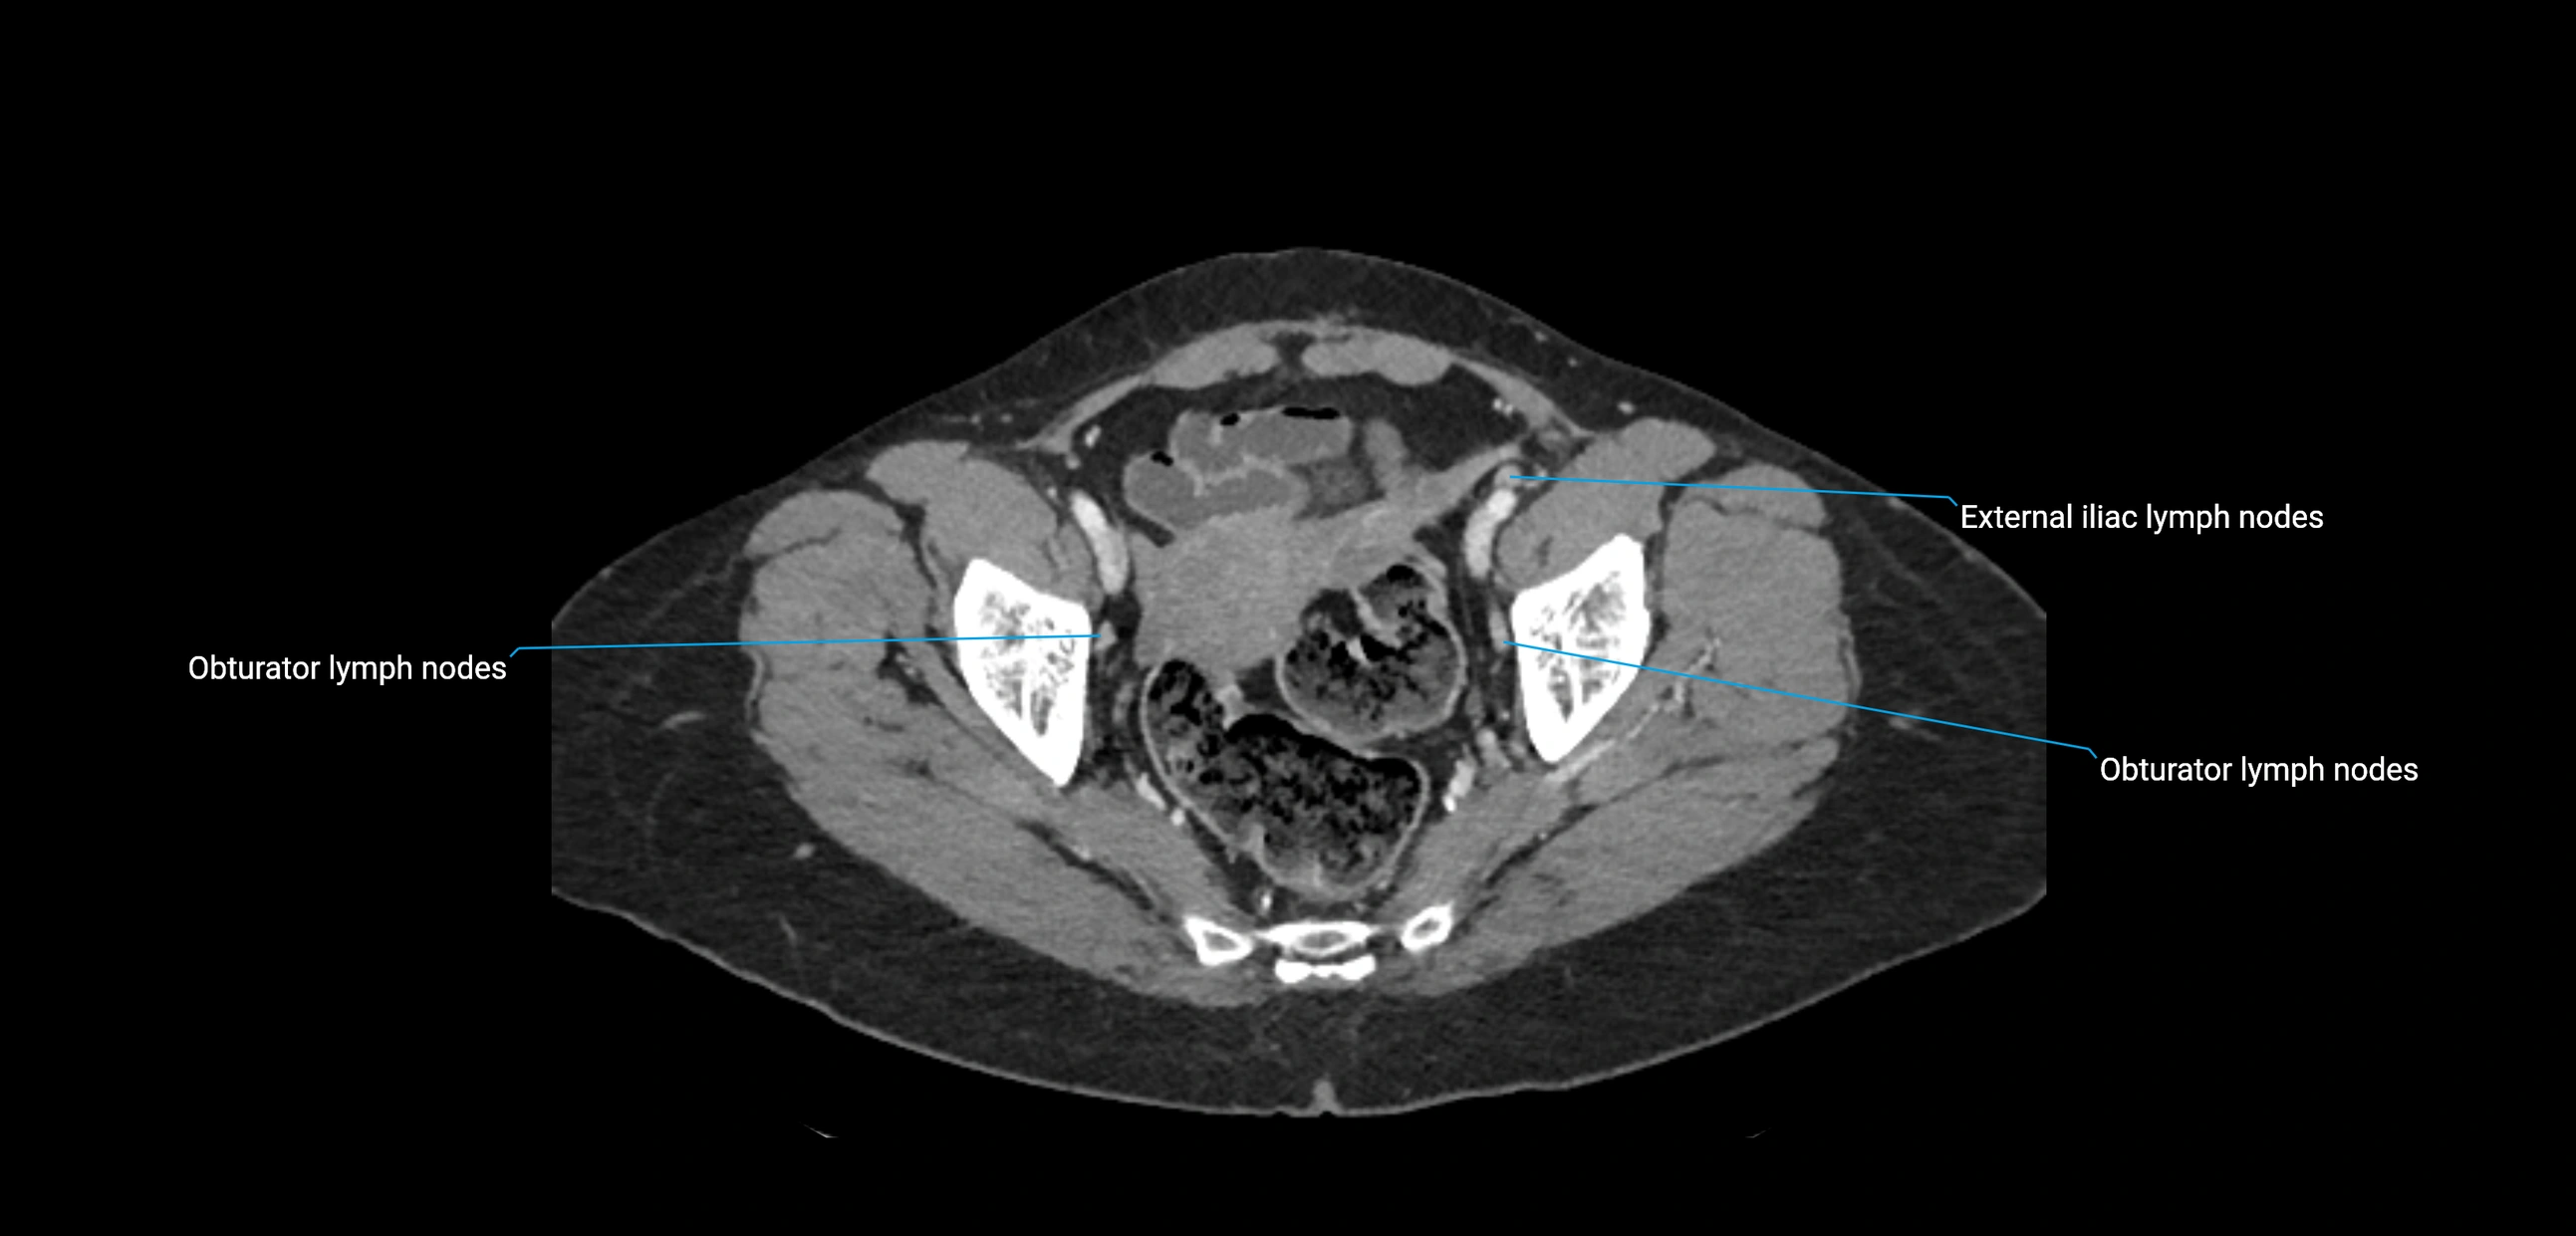

CT Appearance

CT Pre-Contrast:

• Nodes appear as soft-tissue density nodules adjacent to the aorta and IVC

• Calcification may be seen in chronic infections (e.g., tuberculosis)

CT Post-Contrast:

• Normal nodes enhance homogeneously

• Malignant nodes may show heterogeneous enhancement, central necrosis, or conglomerate formation

• Size >1 cm short axis is suspicious, though morphology and distribution are equally important

CT Venography (CTV):

• Demonstrates nodal encasement or compression of adjacent vessels (aorta, IVC, renal veins)

• Useful in staging testicular and ovarian malignancies

• Provides 3D reconstructions for retroperitoneal lymph node dissection planning